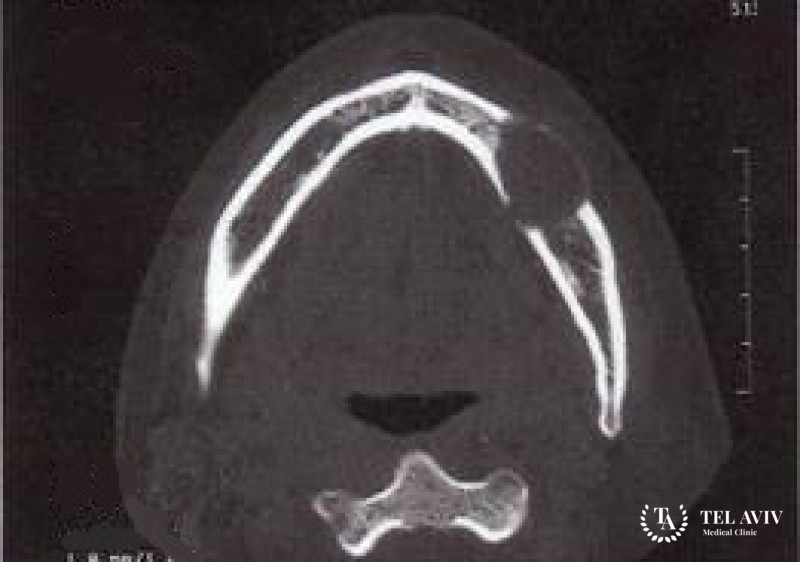

Вначале врач проведет осмотр юного пациента, запишет жалобы и анамнез. Затем будут назначены лабораторные и инструментальны диагностические методы: анализ крови и мочи, компьютерная томография, УЗИ, МРТ. Также необходимо выполнение иммуногистохимического и гистологического исследования образца опухолевой ткани, взятого в ходе биопсии стереотаксическим, пункционным или эксцизионным способом. По результатам полученной информации и визуализации опухолевого участка разрабатывается схема лечения, основанная на стадии онкологического процесса, локализации и размерах очага поражения, тяжести и форме заболевания, состоянии окружающих тканей. Успешное лечение предполагает комплекс действенных мер:

Опухоль формируется из клеток нервного гребня и остатков эмбриональных структур, и развивается у малышей на первых месяцах жизни. Чаще всего новообразование имеет доброкачественную форму. Злокачественный вариант встречается гораздо реже и отличается агрессивным ростом, глубокой инвазией в ствол мозга и основание черепа, повышенным риском рецидивов после удаления прогономы. Локализуется меланотическая нейроэктодермальная опухоль в большинстве случаев в зоне головы и шеи, чаще всего выбирая в качестве очага поражения кости височной ямки или верхней челюсти.